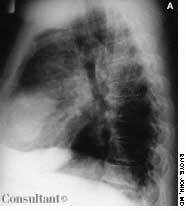

This rash, which covered a 68-year-old woman's body, was noted to have worsened during the past 2 months. A cephalosporin antibiotic had failed to clear the condition. The patient, a nursing home resident, suffered from emphysema, asthma, and heart disease. She had been receiving oxygen therapy and prednisone for 1 year.